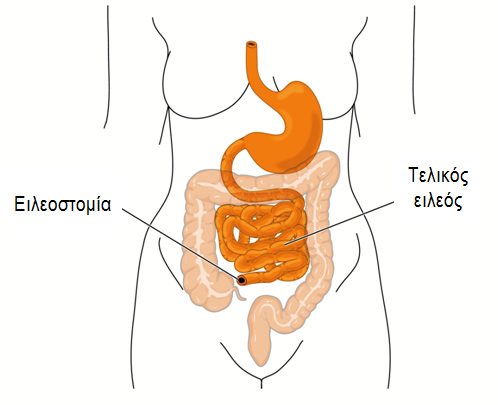

Η νόσος Crohn περιγράφηκε για πρώτη φορά το 1932 από τον Burrill Β. Crohn και τους συνεργάτες του στο Νοσοκομείο Mount Sinai της Νέας Υόρκης. Οι ασθενείς με νόσο Crohn έχουν μία εφόρου ζωής φλεγμονή του γαστρεντερικού σωλήνα, η οποία ξεκινά από την εσωτερική επένδυση του τοιχώματος του, που είναι γνωστή ως βλεννογόνος, και, συνήθως επεκτείνεται και στα βαθύτερα στρώματα του. Η περιοχή στην οποία πιο συχνά αναπτύσσεται η φλεγμονή είναι το σημείο της ένωσης του λεπτού με το παχύ έντερο, δηλαδή εκεί που ο τελικός ειλεός, το τελευταίο τμήμα του λεπτού εντέρου, ενώνεται με το πρώτο τμήμα του παχέος εντέρου, που ονομάζεται τυφλό.

Είτε γίνει «ανοικτά» είτε λαπαροσκοπικά, η χειρουργική επέμβαση κοιλίας πραγματοποιείται για να αντιμετωπίσει το πάσχον τμήμα του εντέρου. Συνήθως, η προβληματική περιοχή εμφανίζει διάτρηση, απόφραξη ή συρίγγιο. Οι δύο πιο κοινές χειρουργικές επεμβάσεις για τη νόσο Crohn είναι η αφαίρεση του τέλους του λεπτού εντέρου και της αρχής του παχέος εντέρου, επέμβαση που ονομάζεται ειλεοτυφλεκτομή, καθώς και η αντιμετώπιση της στένωσης του εντέρου που προκαλεί την απόφραξη, με επεμβάσεις που ονομάζονται εντερεκτομές ή στενωσοπλαστικές. Σε κάθε περίπτωση σκοπός της επέμβασης είναι η διατήρηση όσο το δυνατόν μεγαλύτερου μήκους εντέρου, ώστε να παραμείνει όσο πιο φυσιολογική γίνεται η λειτουργία του πεπτικού σωλήνα που απομένει.

Μετά την αφαίρεση ενός τμήματος του εντέρου, αν και η άμεση αποκατάσταση της συνέχειας του εντέρου είναι η προτιμητέα τακτική, η κατάσταση του ασθενούς μπορεί, σε κάποιες περιπτώσεις, να μην επιτρέψει τη δημιουργία μιας ασφαλούς αναστόμωσης, οπότε, σε ένα τέτοιο ενδεχόμενο, ο εξειδικευμένος χειρουργός παχέος εντέρου και πρωκτού μπορεί να επιλέξει, αντί της αναστόμωσης, την εκτέλεση στομίας, η οποία, όμως, συνήθως είναι προσωρινή.